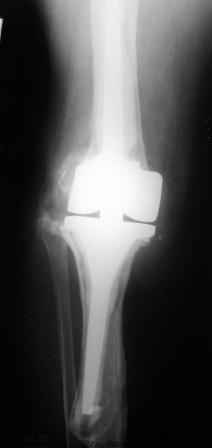

Уважаемые коллеги!Хотелось бы услышать Ваше мнение о возможности и способе помощи больной. 1939 г.р. В 1995г. эндопротезирование правого коленного сустава протезом Феникс, в 1999г. в г. Томске - ревизия - ротационный хинч W.Link. C 2005г. прогрессирует варусная деформация за счетнестабильности тибиального компонента. Попытка ортезирования - без эффекта. Попытка направить в ФСМУ без эффекта, да и больная не хочет никуда ехать.С уважением, Leonid

Понятно что для решения на операцию артродеза необходимы веские причины. Но я не уверен что здесь асептическое расшатывание. Судя по снимкам, бедренный компонент стоит не плохо, и есть рассасывание костной ткани вокруг всего протеза в голени. Что-то мне подсказывает об инфекционном процессе, возможно вялотекущем. В наших условиях я сделал бы обследование включающее анализы крови с СОЭ, СРБ. Сделал бы пункцию коленного сустава или даже биопсию мягких тканей для посева и микроскопии.